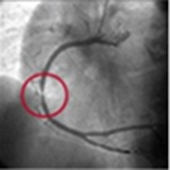

تنگی رگ کرونر راست

بازشدن رگ بعد از آنژیوپلاستی